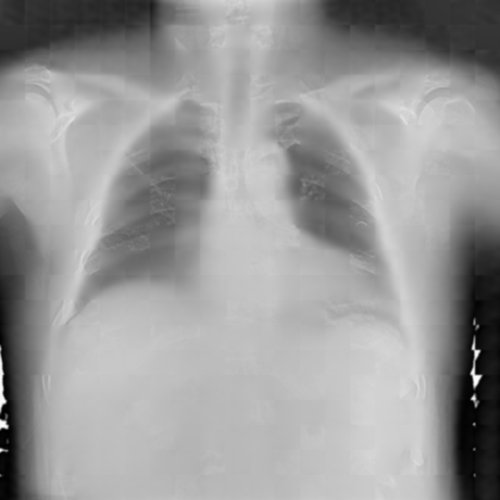

To pre-train a high-performance X-ray foundation model, the first thing we need to do is the collection of large-scale X-ray images. Therefore, a large-scale and high-resolution dataset that contains X-ray medical images is collected for the pre-training. Some representative samples are visualized in Fig. 3.

As shown in Fig. 8, we provide some representative samples predicted by our model. The and column are the raw X-ray images, the and column are masked images, and the and column are the reconstructed images. We can find that our proposed context-aware masking strategy guided MAE framework predict the masked tokens well.

As shown in Fig. 9, given the text lungs, we can find that the activation maps can accurately highlight the target regions. Therefore, we can achieve a higher performance on the downstream tasks. However, the activation maps are imperfect, as the background regions are also highlighted.